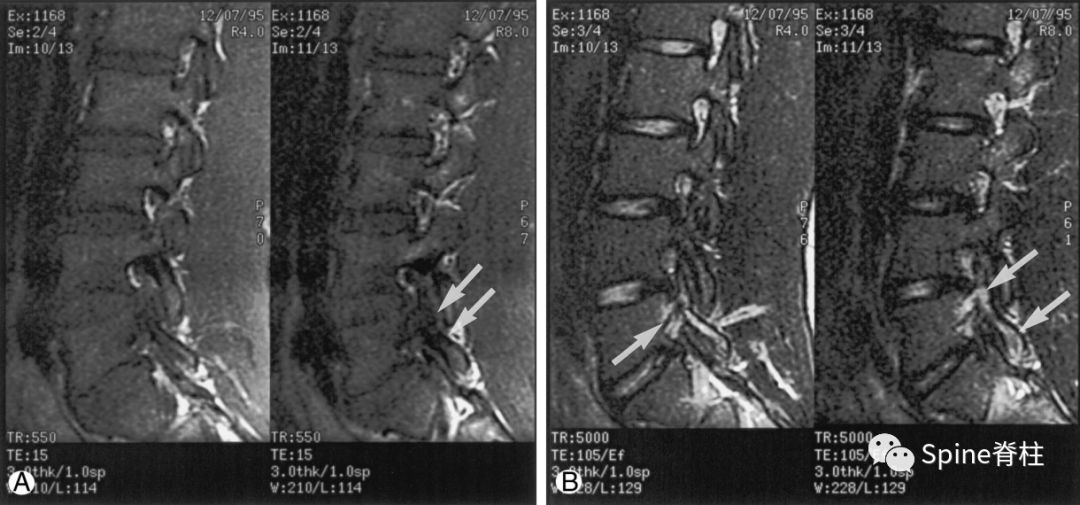

16岁的足球运动员诉右腰部疼痛。A:右侧T1加权像可见腰5峡部和椎弓根呈低信号(箭头);B:右侧T2加权像可见腰5峡部、椎弓根和关节突呈高信号(箭头)。

17岁的篮球运动员诉腰痛。A:T1像,左侧腰3峡部呈不连续的低信号(箭头);B:T2像,左侧腰3椎弓根和峡部呈高信号(箭头)

16岁的足球运动员,诉腰痛,以左侧为重。A:T1像可见腰5左侧峡部完全断裂(箭头);B:T2像,腰5左侧峡部、椎弓根和关节突水肿信号(箭头)

13岁运动员,左侧腰骶部疼痛。A:T1像,左侧腰5峡部完全断裂(箭头);B:T2像,左侧腰5峡部清晰可见,骨质无信号改变,峡部缺损处可见轻微的高信号,提示可能为肉芽组织或积液